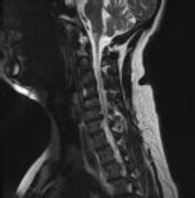

Preoperative MRI images are shown from a 67-year-old woman with neck pain, bilateral upper extremity paresthesias, progressively worsening balance, several falls, and increasing problems in both hands with dropping objects. Figure 1 is a sagittal view, Figure 2 is an axial cut at C2-3, Figure 3 is an axial cut at C5-6, and Figure 4 is an axial cut at C6-7. The patient’s motor strength is grade 4+ of 5 in the bilateral upper extremities.

What is the best next step?

4. Posterior decompression and fusion Discussion: D

The patient has degenerative changes with central and foraminal stenosis from C2-7, including spinal cord compression at C2-3, C5-6, and C6-7. Her progressively worsening balance, falls, and clumsiness are consistent with cervical spondylotic myelopathy. Given the progressive nature of the neurologic symptoms, surgery is recommended for patients with worsening

symptoms. Physical therapy potentially could provide pain relief but would not address the spinal cord compression. Cervical epidural steroid injection is not recommended because of the increased neurologic risk in the setting of substantial spinal cord compression. Given the multiple levels involved and the extension to the C2-3 level, an anterior approach would increase the risk of morbidity and pseudarthrosis compared with the posterior approach, which would allow adequate decompression of the central and foraminal stenosis.

Surgery for cervical myelopathy is performed to decompress the spinal cord, stabilize the spine, and prevent further neurologic injury. Most patients obtain considerable pain relief and some improvement in balance and clumsiness, depending on the severity of the symptoms. Complete resolution of all symptoms should not be expected.

CLINICAL SITUATION

What is the most likely outcome following treatment for this condition?

4. Restoration of strength and balance, paresthesias and clumsiness to normal Discussion: C

The patient has degenerative changes with central and foraminal stenosis from C2-7, including spinal cord compression at C2-3, C5-6, and C6-7. Her progressively worsening balance, falls, and clumsiness are consistent with cervical spondylotic myelopathy. Given the progressive nature of the neurologic symptoms, surgery is recommended for patients with worsening symptoms. Physical therapy potentially could provide pain relief but would not address the spinal cord compression. Cervical epidural steroid injection is not recommended because of the increased neurologic risk in the setting of substantial spinal cord compression. Given the multiple levels involved and the extension to the C2-3 level, an anterior approach would increase the risk of morbidity and pseudarthrosis compared with the posterior approach, which would allow adequate decompression of the central and foraminal stenosis.

Several days following treatment, weakness of grade 2 of 5 develops in the right deltoid and biceps. What complication most likely caused this change?

4. Normal natural history Discussion: B

The postoperative loss of strength in the bicep and deltoid are consistent with C5 nerve palsy, which occurs in 0% to 30% of patients following cervical decompression surgery. Commonly, symptoms occur several days postoperatively. No findings suggested infection, and infection would not lead to these symptoms. A transection of the nerve likely would have been identified during surgery, would have caused immediate symptoms, and is much less common than C5 nerve palsy. Most patients achieve near complete resolution of symptoms within 6 months without further surgical intervention, but the process can take more than 12 months in some cases. No improvement is rare. Oral or injectable steroids and revision surgery are not indicated.

What is the most appropriate treatment for this complication?

4. Revision surgery Discussion: A

The patient has degenerative changes with central and foraminal stenosis from C2-7, including spinal cord compression at C2-3, C5-6, and C6-7. Her progressively worsening balance, falls, and clumsiness are consistent with cervical spondylotic myelopathy. Given the progressive nature of the neurologic symptoms, surgery is recommended for patients with worsening symptoms. Physical therapy potentially could provide pain relief but would not address the spinal cord compression. Cervical epidural steroid injection is not recommended because of the increased neurologic risk in the setting of substantial spinal cord compression. Given the multiple levels involved and the extension to the C2-3 level, an anterior approach would increase the risk

of morbidity and pseudarthrosis compared with the posterior approach, which would allow adequate decompression of the central and foraminal stenosis.

What is the most likely outcome of this complication?

4. Permanent condition with no recovery Discussion: B

The postoperative loss of strength in the bicep and deltoid are consistent with C5 nerve palsy, which occurs in 0% to 30% of patients following cervical

decompression surgery. Commonly, symptoms occur several days postoperatively. No findings suggested infection, and infection would not lead to these symptoms. A transection of the nerve likely would have been identified during surgery, would have caused immediate symptoms, and is much less common than C5 nerve palsy. Most patients achieve near complete resolution of symptoms within 6 months without further surgical intervention, but the process can take more than 12 months in some cases. No improvement is rare. Oral or injectable steroids and revision surgery are not indicated.